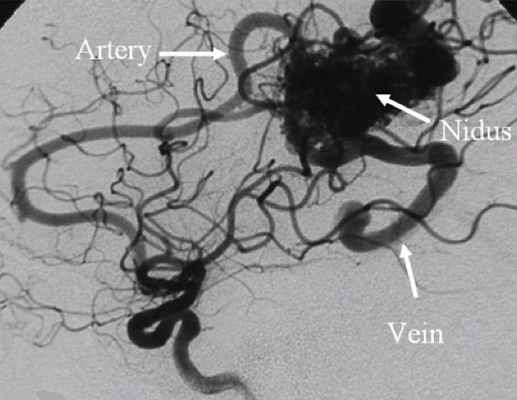

Наиболее важным методом диагностики врожденных артериовенозных свищей является ангиография. Различают прямые и косвенные ангиографические признаки артериовенозных свищей Наличие на ангиограммах контрастированного соустья или сосудистой полости, сообщающейся с артерией и веной, относят к прямым признакам. Косвенно о наличии свища свидетельствуют одновременное контрастирование артерий и вен, расширение просвета приводящей артерии, обеднение сосудистого рисунка дистальнее расположения артериовенозного свища.